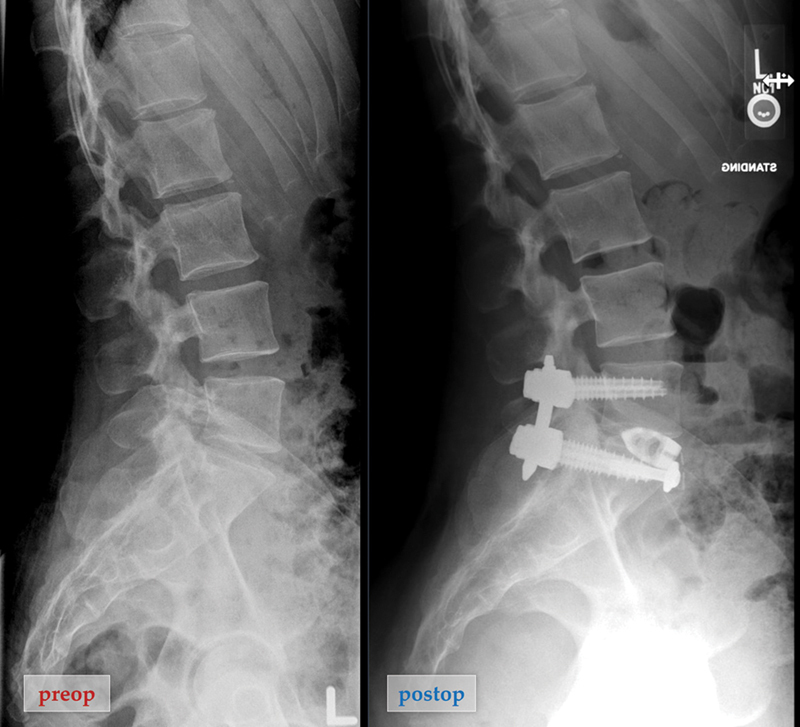

The aim of this study was to demonstrate that anteriorly placed transforaminal lumbar interbody fusion (TLIF) footprint bullet cage is a safe and effective bailout option if difficult left common iliac vein (LCIV) anatomy is unexpectedly encountered during the L5-S1 lateral anterior lumbar interbody fusion (L-ALIF). This retrospective case series includes four patients who received anteriorly placed TLIF cages at L5-S1 during L-ALIF surgery. Demographics, complications, and clinical/radiographic results were collected. The analysis included four female patients with a mean age of 59.0 years and mean body mass index (BMI) of 23.9. Three patients had degenerative conditions and one patient had a deformity. All the patients had an LCIV obstructing the center of the L5-S1 disk space, and titanium TLIF bullet cages were placed and secured with washers and screws. The L5-S1 segmental lordosis increased by 8.3 ± 6.1 degrees with a final mean lordosis of 23.5 ± 8.4 degrees; the L5-S1 intradiskal angle increased by 12.0 ± 7.0 degrees with a final mean disk angle of 18.8 ± 7.0 degrees; the posterior disk height increased by 4.4 ± 2.7 mm with a final mean disk height of 8.0 ± 2.1 mm. The mean numerical rating scale (NRS) for back pain improved by 5.3 ± 2.5 and the mean NRS leg pain improved by 7.7 ± 2.5 over a mean follow-up of 14 months (range: 6-20). There have been no perioperative complications or implant failure to date. If challenging vascular anatomy is encountered during L-ALIF exposure that prevents ALIF footprint cage placement, proceeding with smaller TLIF bullet cage placement anteriorly rather than abandoning the surgical approach is a safe and effective option.